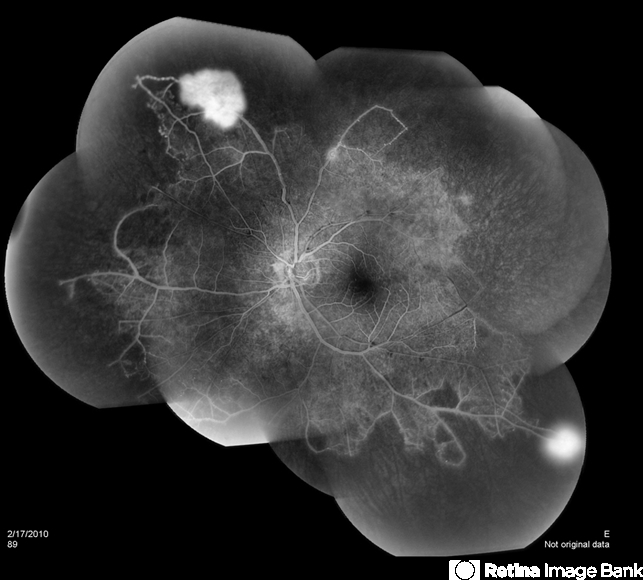

- Susac's syndrome

- 28-year-old man with bilateral Susac's with ischemia and neovascularization.